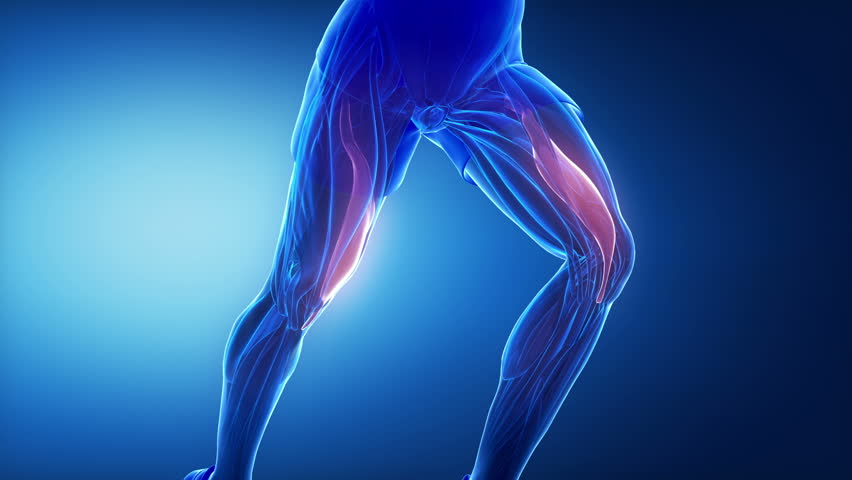

افراد مسن که تمایل به انجام فعالیت های ورزشی دارند، اغلب بواسطه آسیب های استرین اسکلتی – عضلانی از فعالیت بازداشته می شوند. این مسئله تا حدودی بعلت زوال و وخیم تر شدن ویژگی های مکانیکی بافت های پیوندی است که از افزایش سن ناشی می شود. اثرات محافظتی تمرینات مقاومتی روی حفظ سفتی تاندون و لیگامنت و مقاومت نسبت به افزایش نیروها ممکن است احتمال بروز آسیب های استرین تاندونی را کاهش دهد. بعلاوه، از آنجاییکه تاندون ها ساختارهایی از بافت پیوندی هستند که عضله را به استخوان متصل می کنند، آنها می توانند بر سرعت انتقال نیروی انقباض عضلانی تأثیر بگذارند.

افزایش سفتی تاندون بوسیله تمرینات ورزشی مقاومتی که وابسته به توسعه سریع تر گشتاور مفصلی است بروز پیدا می کند. فعالیت های اساسی که نیاز به تولید سریع گشتاور مفصلی دارند، نظیر افزایش میزان تعادل بهمراه انجام فعالیت های ورزشی که در برگیرنده برنامه های تمرینات مقاومتی باشند می توانند بهبود یابند.

لیگامنت ها و تاندون ها به حفظ پایداری مفصل کمک می نمایند. همانطوری که تاندون ها و لیگامنت ها مسن می شوند، قابلیت مقاومت در برابر بارهای کششی (Tensile) آنها کاسته می شود، در نتیجه اثر کمتری در پایداری مفصل در پاسخ به نیروهای تکراری یا زیاد خواهند داشت که در طی فعالیت های اساسی رخ می دهند.

عدم پایداری مفصل در طی حرکت در مکانیک غیر طبیعی مفصل ایجاد می گردد. این دگرگونی در مکانیک مفصل ممکن است در اثر استرس های فزاینده روی ساختارهای مفصلی ایجاد گردد و منجر به زوال مفصل بیمار گردد.